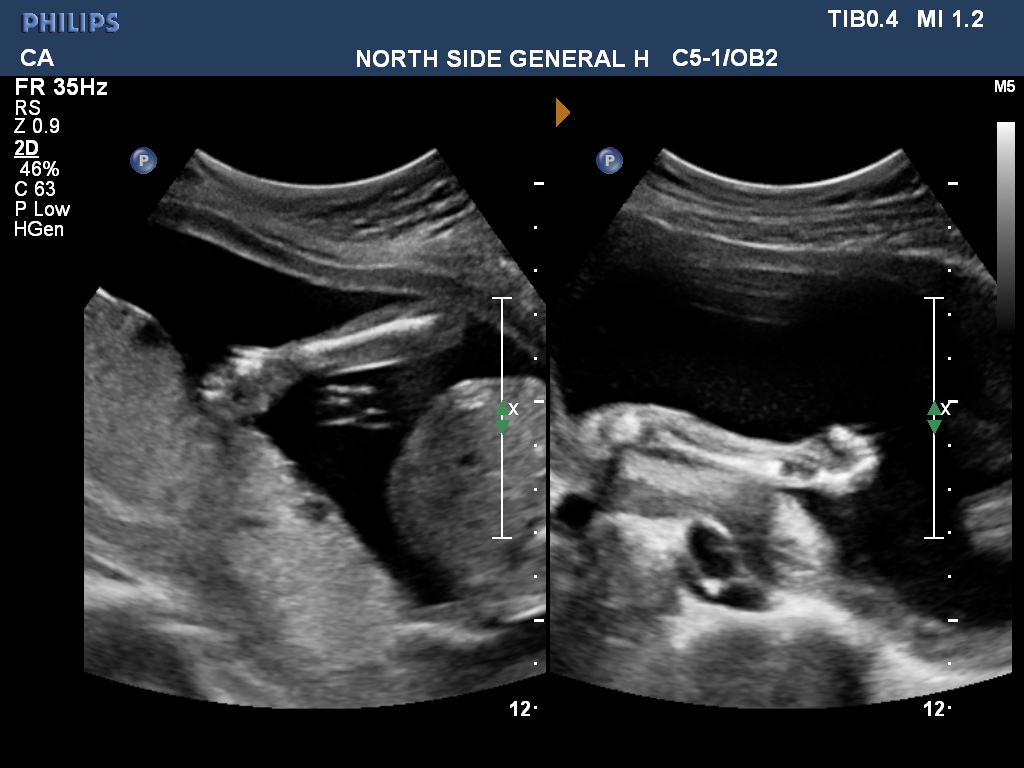

Just for fun because I don't think there are any clues here. And not sure what I'm looking at in #3 :lol: I didn't ask the tech b/c I want to be surprised since this is our last but guessing is fun :) ETA - This is from today 20 weeks 5 days.

Attachment 39423

Going off skull shape... i guess a girl.☺️

No gender clues in these. Congrats!!!